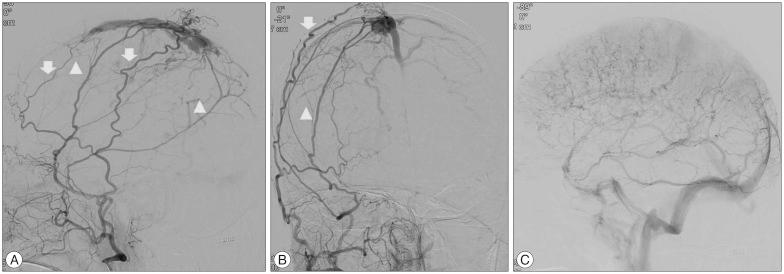

A 66-year-old woman presented with intermittent paraparesis and generalized tonic-clonic seizure. Cerebral angiography demonstrated dural arteriovenous fistula (AVF) involving superior sagittal sinus (SSS), which was associated with SSS occlusion on the posterior one third. The dural AVF was fed by bilateral middle meningeal arteries (MMAs), superficial temporal arteries (STAs) and occipital arteries with marked retrograde cortical venous reflux. Transfemoral arterial Onyx embolization was performed through right MMA and STA, but it was not successful, which resulted in partial obliteration of dural AVF because of tortuous MMA preventing the microcatheter from reaching the fistula closely enough. Second procedure was performed through left MMA accessed by direct MMA puncture following small decortications of cranium overlying the MMA using diamond drill one week later. Microcatheter could be located far distally to the fistula through 5 F sheath placed into the MMA and complete obliteration of dural AVF was achieved using 3.9 cc of Onyx.

一名66岁女性出现间歇性双下肢轻瘫和全身性强直阵挛发作。脑血管造影显示硬脑膜动静脉瘘(AVF)累及上矢状窦(SSS),且与后三分之一的上矢状窦闭塞有关。该硬脑膜AVF由双侧脑膜中动脉(MMA)、颞浅动脉(STA)和枕动脉供血,伴有明显的皮质静脉逆行回流。通过右侧MMA和STA进行了经股动脉Onyx栓塞,但未成功,由于MMA迂曲,微导管无法足够接近瘘口,导致硬脑膜AVF部分闭塞。一周后,使用金刚石钻头在覆盖MMA的颅骨上进行小范围去骨皮质后,通过直接穿刺MMA进入左侧MMA进行了第二次手术。通过置于MMA的5F鞘管,微导管能够置于瘘口远端,使用3.9 cc Onyx实现了硬脑膜AVF的完全闭塞。